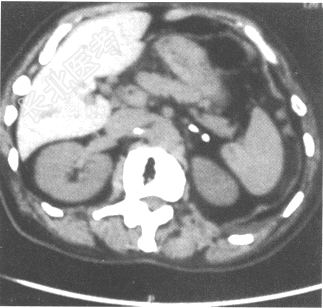

- 简答题1、肾上腺CT:双侧肾上腺可见点状钙化,见下图。促肾上腺皮质激素238.06pg/ml(参考值7.2~63.3pg/ml)。最可能的诊断是什么